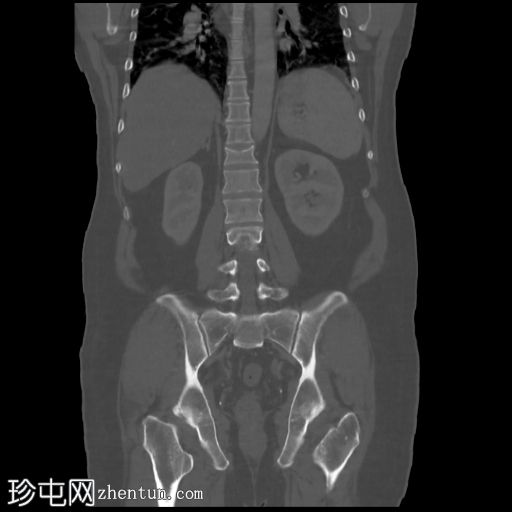

冠状位骨窗

D12椎体陈旧性前压缩性骨折,无移位。